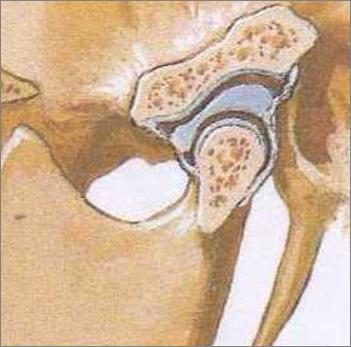

Patologie A.T.M.

L'articolazione temporo mandibolare (ATM) è un'articolazione molto complessa e la sua patologia, causata da disfunzioni muscolari cinetiche (del movimento masticatorio) puo' interessare sia la componente ligamentosa/meniscale (lussazione, sublussazione , incoordinazione meniscale , lassità ligamentosa) , che la componente ossea(artriti , artrosi ). L'ATM è al centro di un complesso sistema che coinvolge ossa-muscolo e denti e quindi una sua patologia pu' determinare ripercussioni molto importanti ed invalidanti di piu' apparati . Per i motivi sopra citati è molto importante diagnosticare precocemente e con estrema accuratezza specialistica (esame gnatologico) i disturbi e le disfunzioni neuro-muscolari dell'atm che molto spesso necessitano di un approccio multidisciplinare (reumatologo, neurologo, fisioterapista...). Nei nostri centri è disponibile la figura dello gnatologo atto alla diagnosi e alla eventuale terapia di queste patologie .